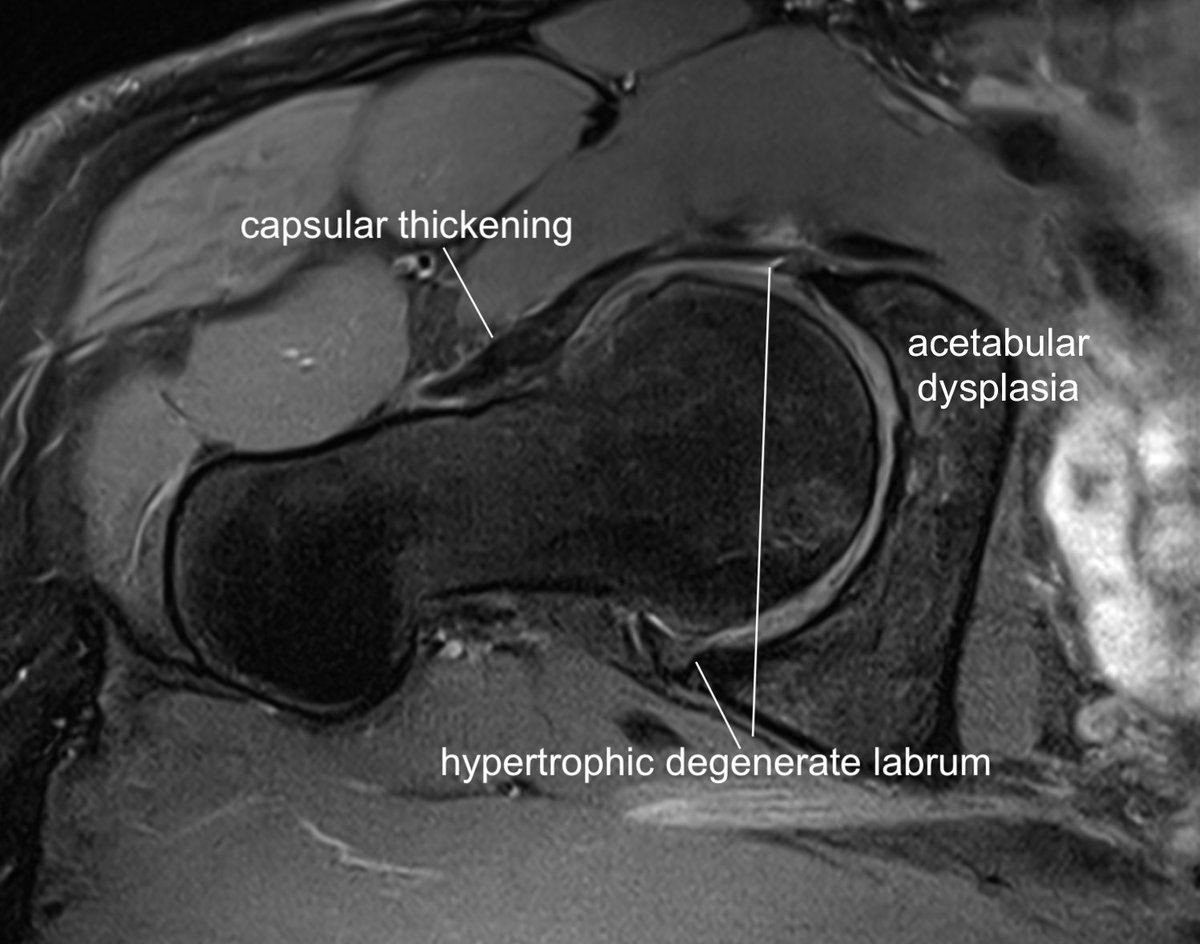

Consent ✅ Right hip pain & stiffness Both hip joints show OA changes - but R more advanced than L Why?